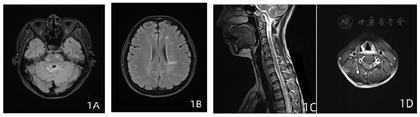

患者,女性,45岁,以"发作性右侧肢体无力、口齿不清"起病,因"发作性右侧肢体无力2年余,加重1周"于2021年4月收住苏州大学附属第二医院。患者2019年2月无明显诱因出现发作性右侧肢体无力、口齿不清,右手持物不稳,右下肢行走拖曳,持续约1 min缓解,发作频率7~8次/d,无饮水呛咳、吞咽困难,无四肢抽搐、意识不清,外院就诊考虑短暂性脑缺血发作,予改善循环治疗无好转,上述症状仍反复发作,后未继续治疗。2020年4月症状较前加重,出现四肢乏力不缓解,行颅脑MRI提示脑室旁脑白质及脑干异常信号,未予治疗。2020年7月患者肢体无力较前进一步加重,行走时跌倒2次,至我院就诊,神经系统查体示:双下肢肌力4级,右侧指鼻试验欠稳准,四肢腱反射亢进,左侧踝阵挛阳性,双侧病理征(-),余无明显阳性体征。头颅、颈胸椎MRI(2020年7月):幕上及幕下脑白质内多发炎性脱髓鞘;C4-6椎体水平颈髓斑片状强化、脑桥及延髓内异常信号影,小脑内异常强化(图1)。脑脊液寡克隆区带阳性(2型)。结合患者病史、体征及影像学表现,依据2017版McDonald MS诊断标准[1],诊断"多发性硬化" 。扩充残疾功能量表(EDSS)评分:1.5分。予甲泼尼龙冲击,联合硫唑嘌呤免疫抑制治疗,出院时患者肢体无力症状减轻,双下肢肌力4+级。2020年11月复查颅脑、颈椎MRI较2020年4月对比,双侧脑室及四脑室旁白质、脑干病灶范围缩小,强化程度明显减低。2021年2月患者右下肢无力再发加重,行走不能,再次入住本院神经科。查体示:右下肢肌力3级,四肢腱反射亢进,双侧踝阵挛阳性,双侧病理征(+)。EDSS评分:3分。完善MRI较(2020年11月)相比:延髓及中脑左侧份新增小斑片状明显强化灶,C2椎体水平颈髓内新增斑片状强化灶;横断位示颈髓内多发斑片状强化灶,余较前相仿。实验室检测未见明显异常。腰椎穿刺压力175 mmH2O(1 mmH2O=0.0098kPa ),常规、生化正常范围。入院后予醋酸泼尼松小剂量口服,联合丙种球蛋白静滴,症状无明显改善,后加用甲泼尼龙500 mg冲击治疗,右下肢无力明显改善,出院时右下肢肌力4+级。患者病情反复,出院1周后右下肢无力再次加重,查体右下肢肌力3级,EDSS评分:2分。拟"高活动性多发性硬化"入住我科。病程中,患者神志清、精神一般,饮食可、睡眠欠佳,大小便正常,体重无明显变化。个人史及家族史无殊。

辅助检查:血尿粪常规、凝血系列、血生化全套、电解质、糖化血红蛋白、叶酸、维生素B12、肿瘤标志物、甲状腺功能、风湿因子、自身抗体初筛等未见明显异常。脑脊液寡克隆区带阳性(2型)。血、脑脊液AQP4抗体阴性。颅脑、颈胸椎MRI(平扫+增强):幕上及幕下脑白质内多发炎性脱髓鞘病灶;C4-6椎体水平颈髓斑片状强化、脑桥及延髓内异常信号影,小脑内异常强化。